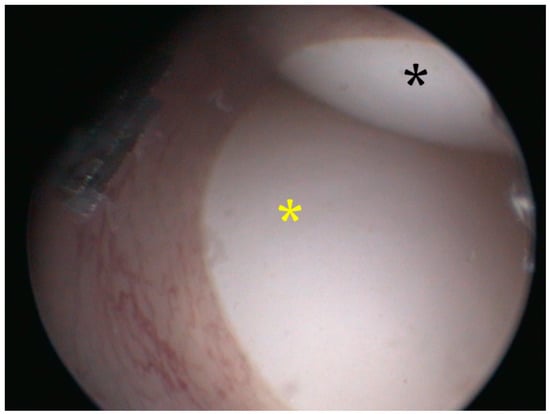

2.2.3. Case 3